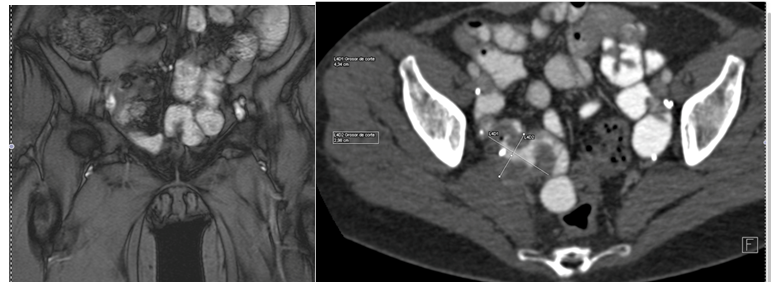

A 54-year old white woman, without significant past medical history other than menopause since 2years ago presented with post coital hematuria and also she had urinary tract infections (UTIs), documented by urine cultures (Proteus Mirabillis). No other associated symptoms. She received antibiotic therapy with quinolones. The urine cytology was negative. The assessment by the Gynecology service was normal. The renal ultrasound (US) Each kidney was normal, preserved cortico medullary differentiation and without dilated collecting systems. There was irregularity zone in the mucosa close to bladder neck, measuring 1x0.5cm. Cystoscopy revealed an edematous and erythematosus lesion of 1x1.5cm in the posterior wall of the bladder neck that extended into the urethra. In pelvic magnetic resonance imaging (MRI) a pelvic mass was evident measuring 35x38x47mm, widening the bladder neck at this level, nonspecific inguinal adenopathies and a left iliac node with malignancy aspect.

The pelvic examination during the transurethral resection of bladder (TURB) revealed a palpable nodule on the anterior wall of the vagina and there was not others remarkable findings. The pathology of transurethral resection of bladder confirmed urethra adenocarcinoma muscle-invasive with invasion of bladder neck. She was taken to an extension study (toracoabdominopelvic scan) in which the metastatic lesions were discarded (Figure 1-3).

Figure 3 Initial pelvic MRI

Figure 4 Initial pelvic MRI.